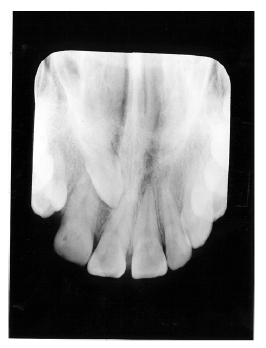

Figure 2 illustrates advanced enamel caries on the mesial surface of the premolar.

Figure 2 - Advanced Enamel Caries

Figure 2